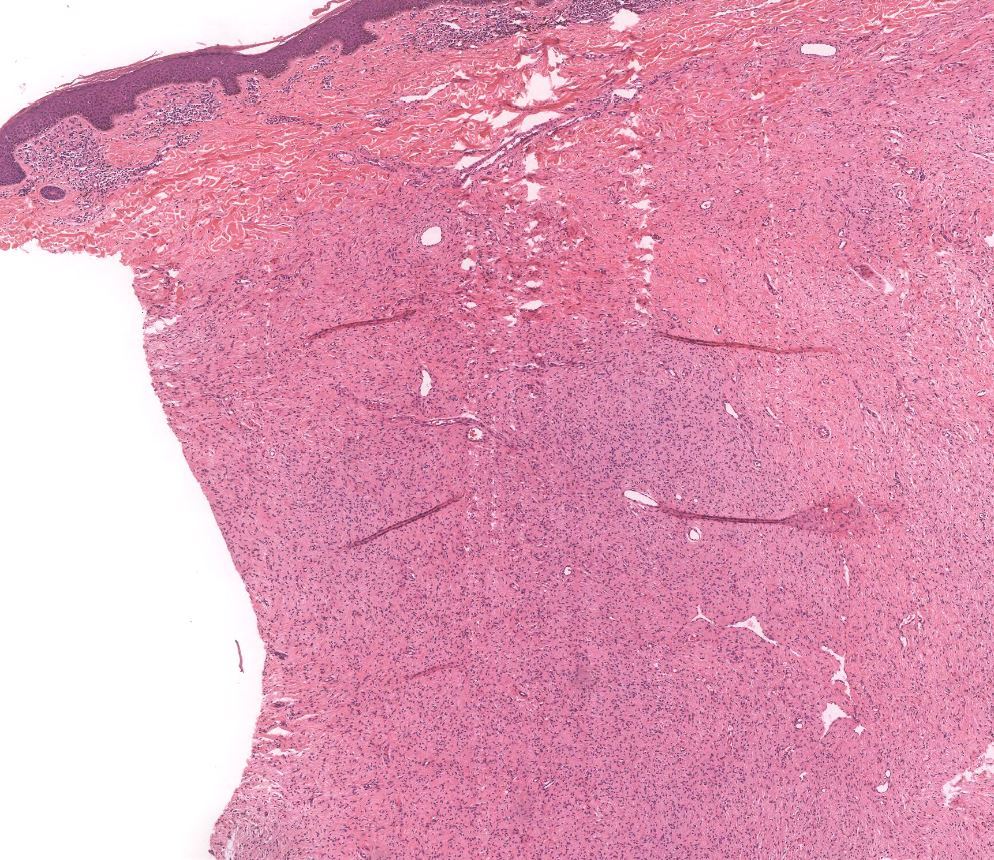

Cellular Blue Nevus